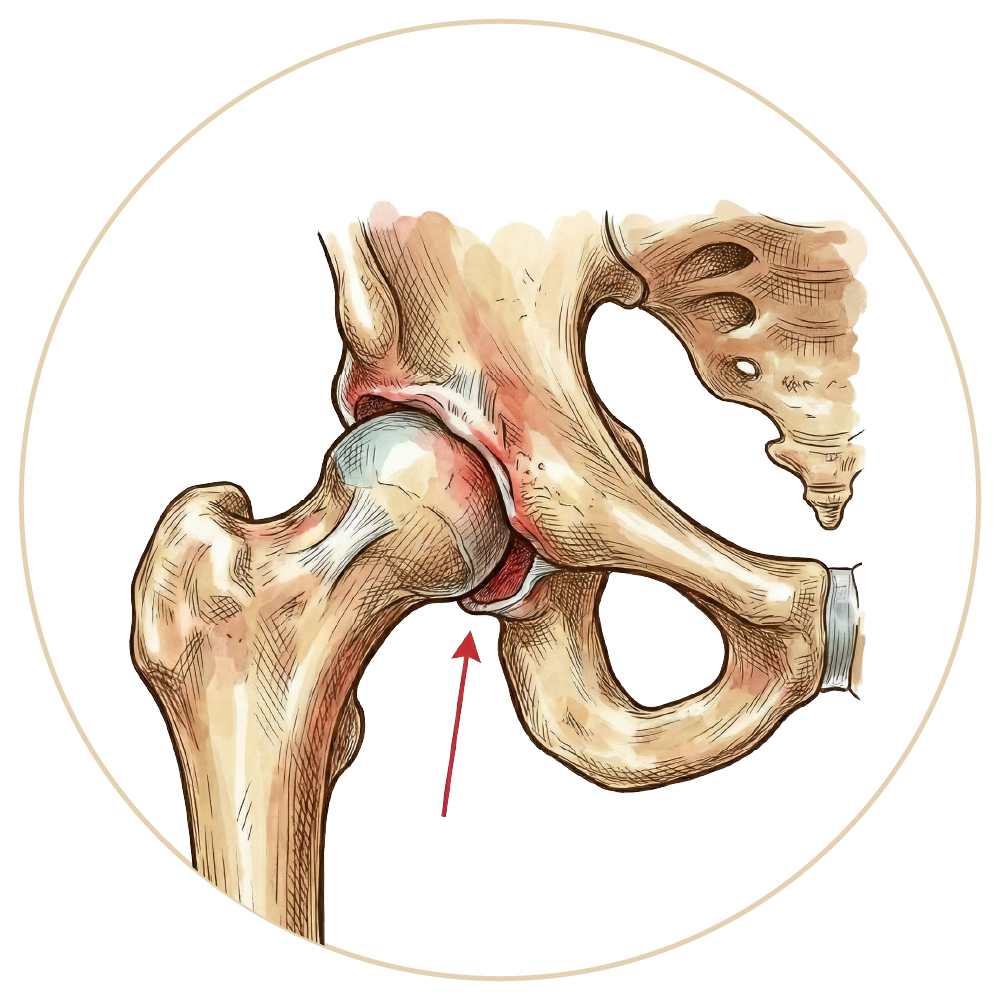

Kalça Sıkışma Sendromu

Travmatik Kalça Çıkığı

Kalça Artroskopisi

Kalça Protezi

Robotik Kalça Protezi